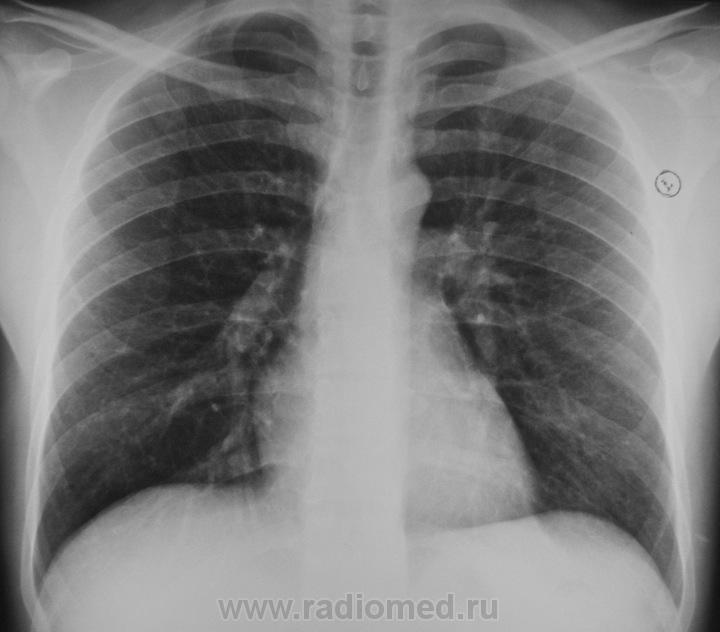

Правый КДС и лег рис справа - немного заинтерсовали. Но для грыжесечения, думаю, значения не имеют. "Норма" --->> "По месту .... сравнить с Фл-архивом".

А почему снимок такой "темный"? Почему лопатки полностью наслаиваются на легочные поля. Может лаборант выполняет укладку установку пациента не правильно?

Обратите внимание на первое ребро.

Обратили.На фоне ребра не совсем понятные полостюшки( полостями язык не поворачивается назвать).

Для начала я бы убедился, что это не артефакт и не игра теней.

Не исключено , что в ребре литические очаги .

Это не артефакт, на самом деле в 1-ом ребре есть литический очаг.

Четкое отграничение от неизмененной окружающей ткани - что-то не серьезное. Или беспокоит?

Хотя бы заднюю проекцию прицельно в рёберном режиме доснять...

Покажите другие снимки. Откуда стрельнуло или чего?